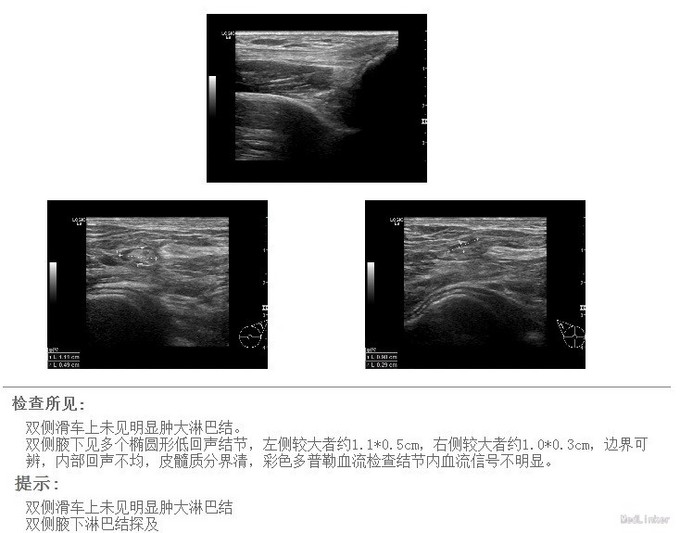

进一步扫全身多处的淋巴结、均有肿大 初步排除cancer,转呼吸内科进一步诊治。 呼吸内科的EBUS-TBNA技术的日趋成熟,对于外科术前分期、判断非常有价值。随着诊疗的个体化呼声越来越高,内、外、病理、影像、放化疗组成的综合肺部肿瘤诊治中心发展前景很大